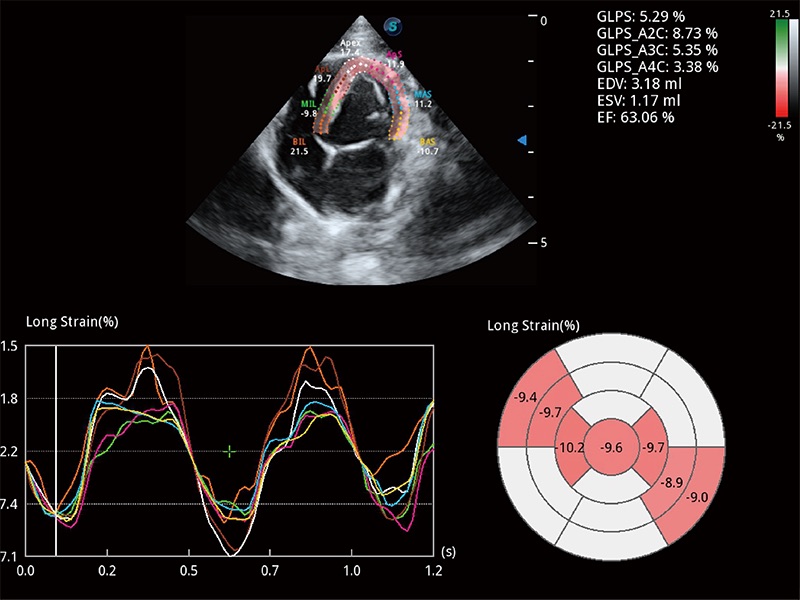

通过心肌识别技术与二维斑点追踪技术相结合,对心脏的超声图像进行量化分析。计算心肌17个节段的应变、应变率、速度、位移等,并通过牛眼图的形式进行呈现。

通过360度任意调节3条M型取样线,在同一心动周期上观察心脏不同位置的运动曲线,得到准确的心功能测量数据,有效评估心肌运动及左心室功能。

具备多种协议可选,同时支持17阶段划分法和专业的SE报告。

能够基于左心室壁追踪和辛普森法,自动计算射血分数,支持多个可移动点描迹,与手动测量相比,极大节省了动物医生的时间和精力。